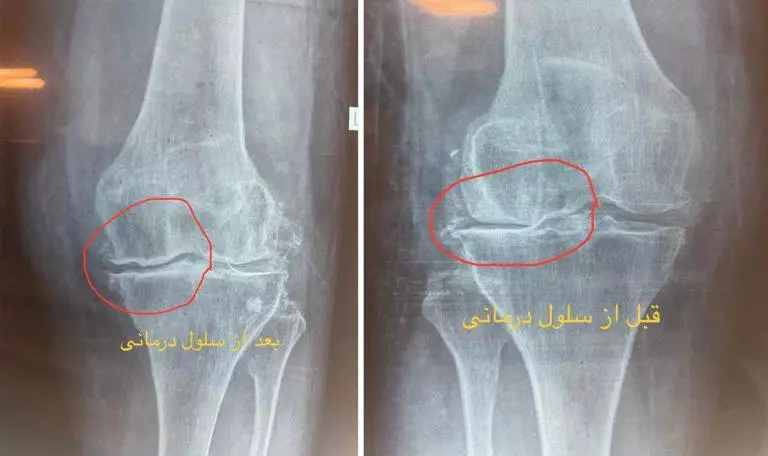

بهترین روش درمان آرتروز زانو با تزریق سلول بنیادی به مفصل زانو

این درمان غیرتهاجمی می باشد و برای مشکلاتی مانند استئوآرتریت، آسیبهای غضروفی و التهابهای مزمن مفصلی کاربرد دارد. مطالعات نشان میدهد که در 80تا 90درصد موارد، بهبود قابل توجهی در عملکرد مفصل مشاهده میشود،پزشکان و متخصصین این روش را به عنوان جایگزینی مناسب برای جراحیهای سنتی در نظر میگیرند.

براساس آخرین پژوهشهای انجمن ارتوپدی آمریکا (AAOS 2023)، سلول درمانی زانو با نرخ موفقیت ۸۹% در آسیبهای درجه ۲، مؤثرترین روش غیرجراحی شناخته شده است